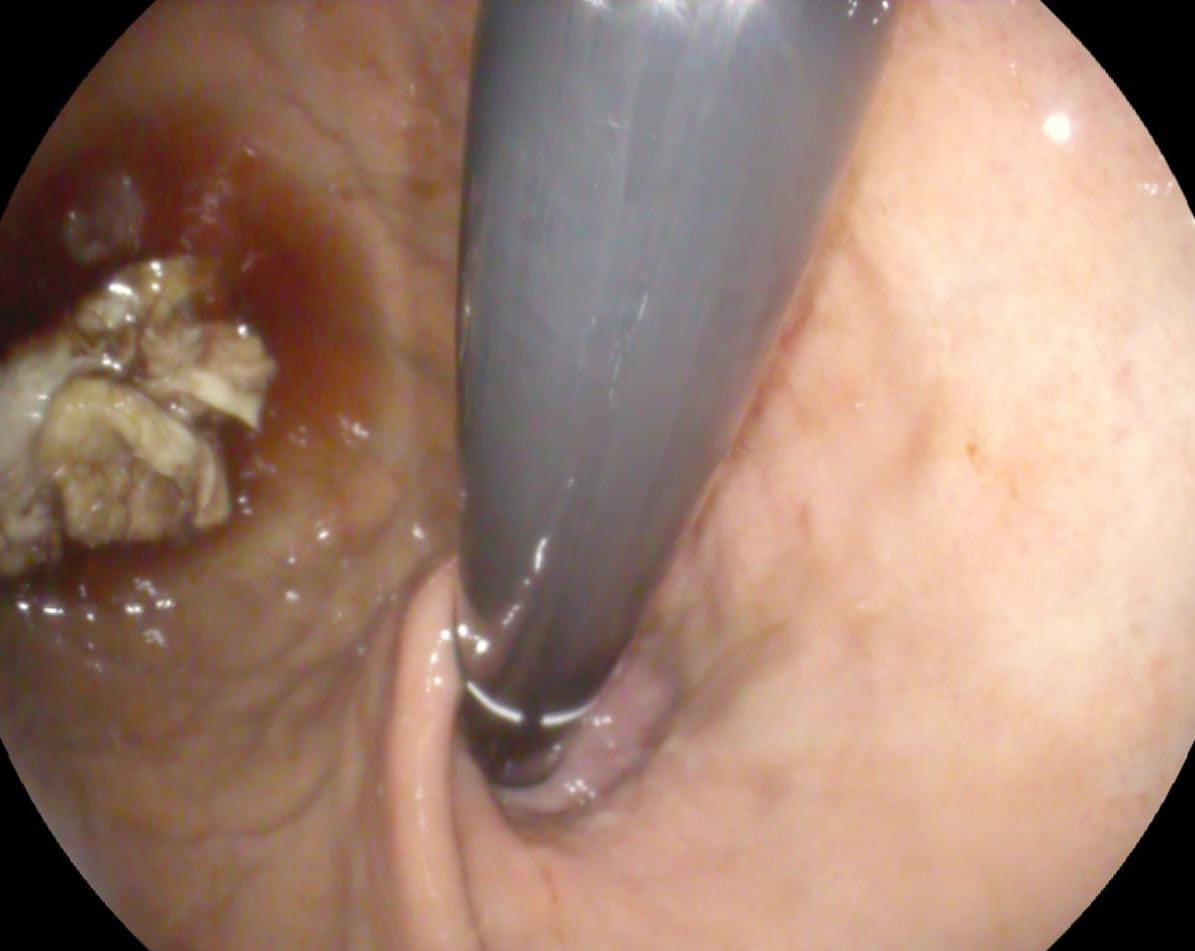

استقبل الفريق الطبي بقسم المناظير بمستشفى أبو كبير المركزي مواطن يبلغ من العمر ٧٠ عامًا، يعاني من صعوبة في البلع؛ نتيجة انسداد مجري الطعام بسبب ابتلاع قطعة لحم كبيرة بداخلها عظمة علقت أسفل صمام المريء العلوي.

على الفور تم استدعاء فريق طوارئ المناظير، وتم عمل منظار معدة تشخيصي طوارئ حيث تم تفتيت قطعة اللحم واستخراج العظمة وأجزاء من قطعة اللحمة، وتحريك المتبقي لتجويف المعدة، وإزاحة الانسداد، كما تم عمل منظار تشخيصي كامل للحالة حتى الإثنى عشر، وبعد الانتهاء من الفحص تبين وجود تحور في نسيج المرئ العلوي، وتم أخذ عينات وإرسالها للتحليل الباثولوجي، وخروج المريض بسلام بعد كتابة العلاج والإرشادات اللازمة له.